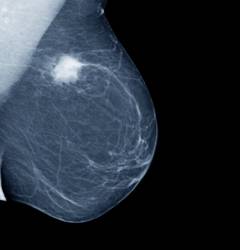

- Маммография – рентгеновские снимки молочной железы для выявления уплотнений. Современным методом является цифровая маммография.

| Рентгеновская маммография | Рентгеновское исследование молочной железы с низкой интенсивностью излучения. Маммография – основной метод ранней диагностики злокачественных новообразований с точностью 92%. В Европе регулярно проводится всем женщинам старше 45 лет. В России – женщинам старше 40 лет. | Исследование проводится как обычная рентгенография. Женщина обнажается по пояс, прислоняется к столику, кладет молочную железу, после чего делают снимок. | |

| Рентгеновская маммография | Рентгеновское исследование молочной железы с низкоинтенсивным излучением. Это основной метод раннего выявления злокачественных опухолей с точностью 92%. В Европе применяется для женщин старше 45 лет, в России — старше 40 лет, хотя не все проходят обследование. Эффективно выявляет опухоли размером от 2 до 5 см. Большое количество кальцинатов (более 15 на см²) служит основанием для дальнейшего обследования. | Процедура аналогична обычной рентгенографии: женщина обнажается по пояс, прижимается к столику, на который укладывается молочная железа, и делают снимок. Аппараты должны соответствовать стандартам ВОЗ. Виды: * пленочная – используется кассета с пленкой; * цифровая – изображение сохраняется на компьютере. | |